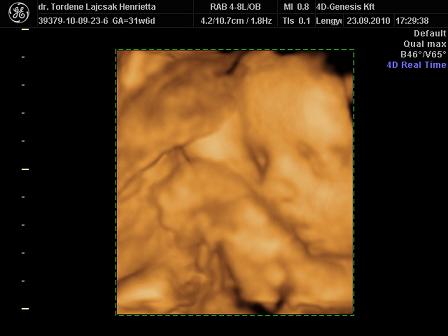

tegnap voltunk Uh-n. minden rendben van vele, egyre nagyobb. :)

méreteink:

BPD: 79,7 mm

HC: 292,5 mm

AC: 268,5 mm

FL: 57,8 mm (ezt nem tudta pontosan lemérni, mert érdekesen pózolt )

súly: 1700 g. (netes kalkulátor alapján 1750)

rakok róla néhány képet. :oops: és már 32 hetesek vagyunk...lassan finish.. :)